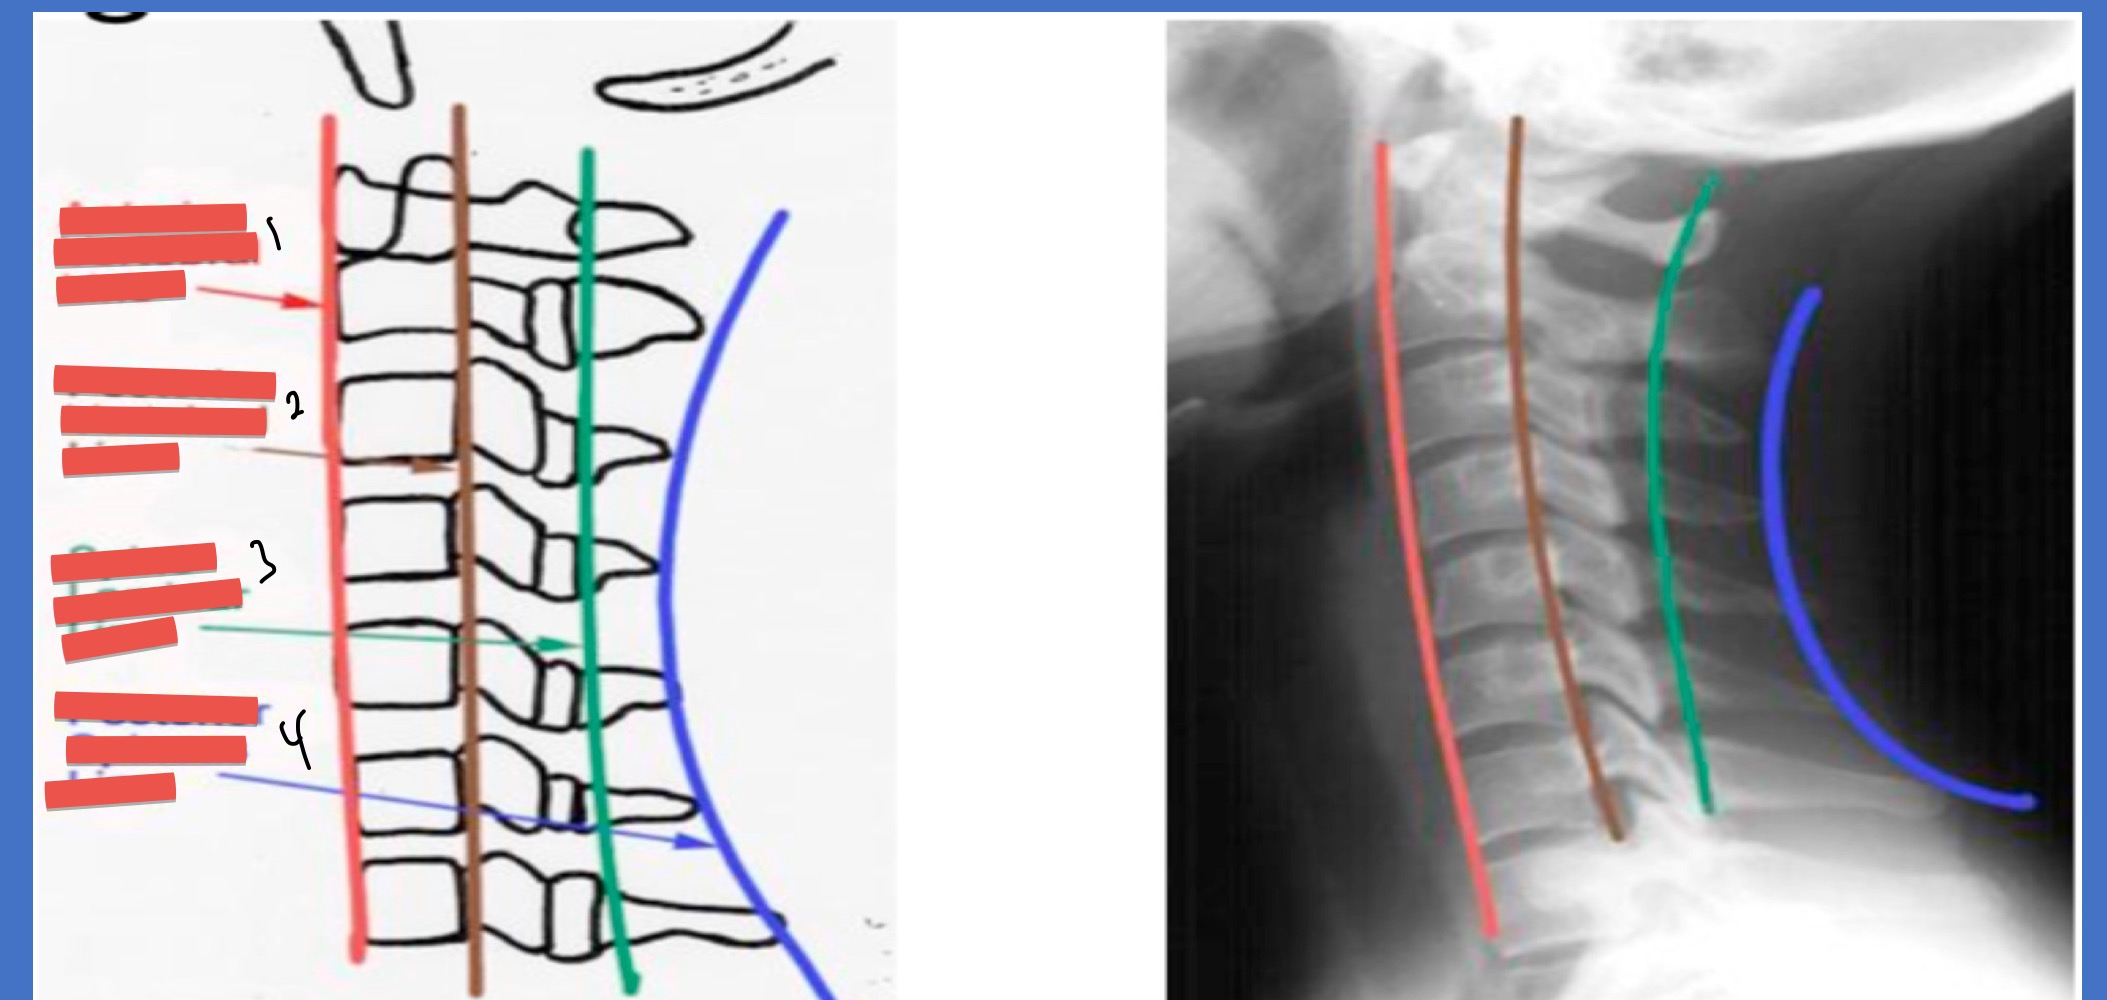

Name the lines 1-4

Ant vertebral line

post. vertebral line

spino-laminar line

post. spinous line